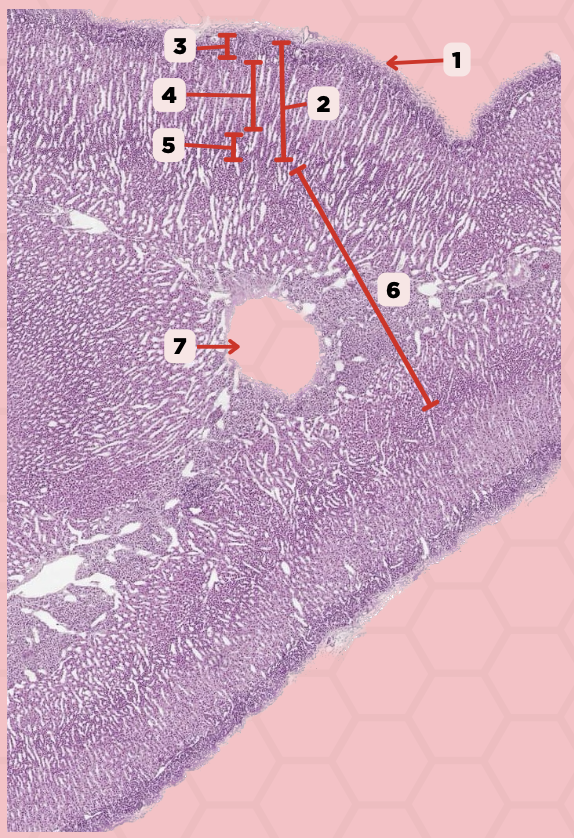

Adenohypophysis

What does #1, #4, and #5 form?

Pituitary

Identify the specimen.

Intermediate Lobe

Identify the structure labeled as 1.

Posterior Lobe

Identify the structure labeled as 2.

Pituitary Stalk

Identify the structure labeled as 3.

Pars Tuberalis

Identify the structure labeled as 4.

Anterior Lobe

Identify the structure labeled as 5.

Neural Ectoderm

What ectoderm is #2  derived from?

Oral Ectoderm

What ectoderm #1, #3, & #4 derived from?